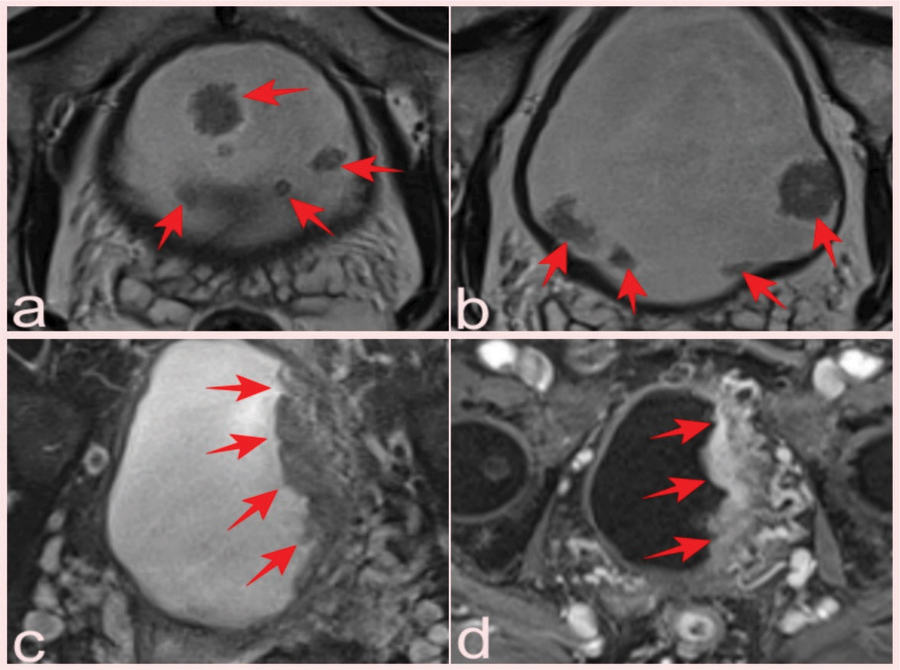

Figure 4

(a, b) Two slices from T2-WI of a 69-year-old patient who presented with elevated PSA and had a total of 10 lesions with pTa pathology, four of which were reported as VI-RADS 1 and six as VIRADS 2 (arrows). Fat-suppressed T2-WI (c) and (d) DCE images of a 75-year-old man with a serum PSA value of 8.9 ng/mL and Gleason score of 3 + 3 prostate cancer, with a lesion reported as VI-RADS 5 but pathologically as a high-grade pT2 tumor (arrows).